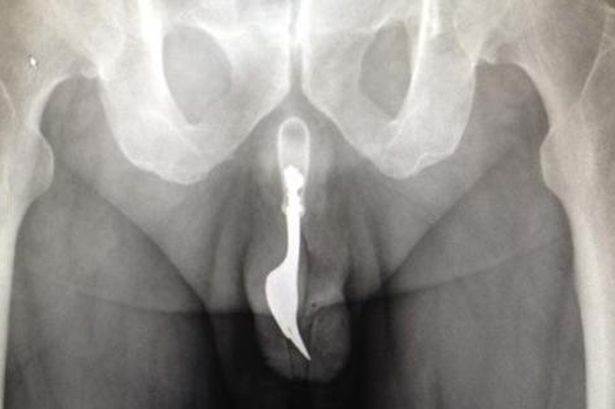

image

The Funny Images Thread